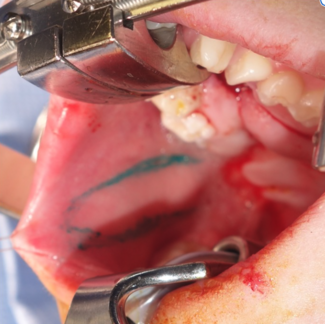

Buccinator-based regional flaps (BMMF, FAMM) provide vascularized options for cleft-related oronasal fistula repair when palatal tissue is limited, emphasizing anatomy, design, and flap selection.

Molly MacIsaac, BS; Alexzandra Mattia, BS; Jordan Halsey, MD; S. Alex Rottgers, MD